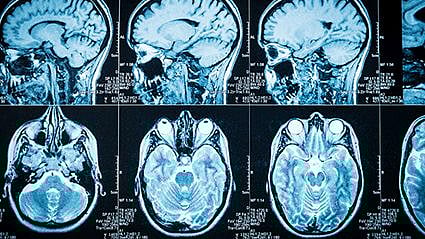

La forma típica de diagnosticar el Parkinson es con una IRM del cerebro. Pero los investigadores argumentan que este escáner no tiene la sensibilidad suficiente, y no puede revelar algunos de los cambios biológicos que se producen en el cerebro de estos pacientes. Más bien, las IRM se usan de forma más frecuente para descartar otros diagnósticos.

Ahora, unos científicos de la Universidad Hebrea de Jerusalén, en Israel, trabajaron en una forma distinta de diagnosticar la enfermedad, llamada IRM cuantitativa (IRMc). Las IRMc observaron una parte del cerebro profundo llamada cuerpo estriado, que ayuda al movimiento voluntario del cuerpo y que se deteriora rápidamente con la progresión de la enfermedad.

Los resultados, que se publicaron en la edición del 15 de julio de la revista Science Advances, encontraron que su análisis de la IRMc, una técnica que compararon con tomar la misma fotografía con diferente iluminación, pudo mostrar los cambios en la estructura del tejido dentro de las diferentes secciones del cuerpo estriado. Antes, esta técnica solo se habría podido observar en pruebas de laboratorio tras la muerte del paciente.